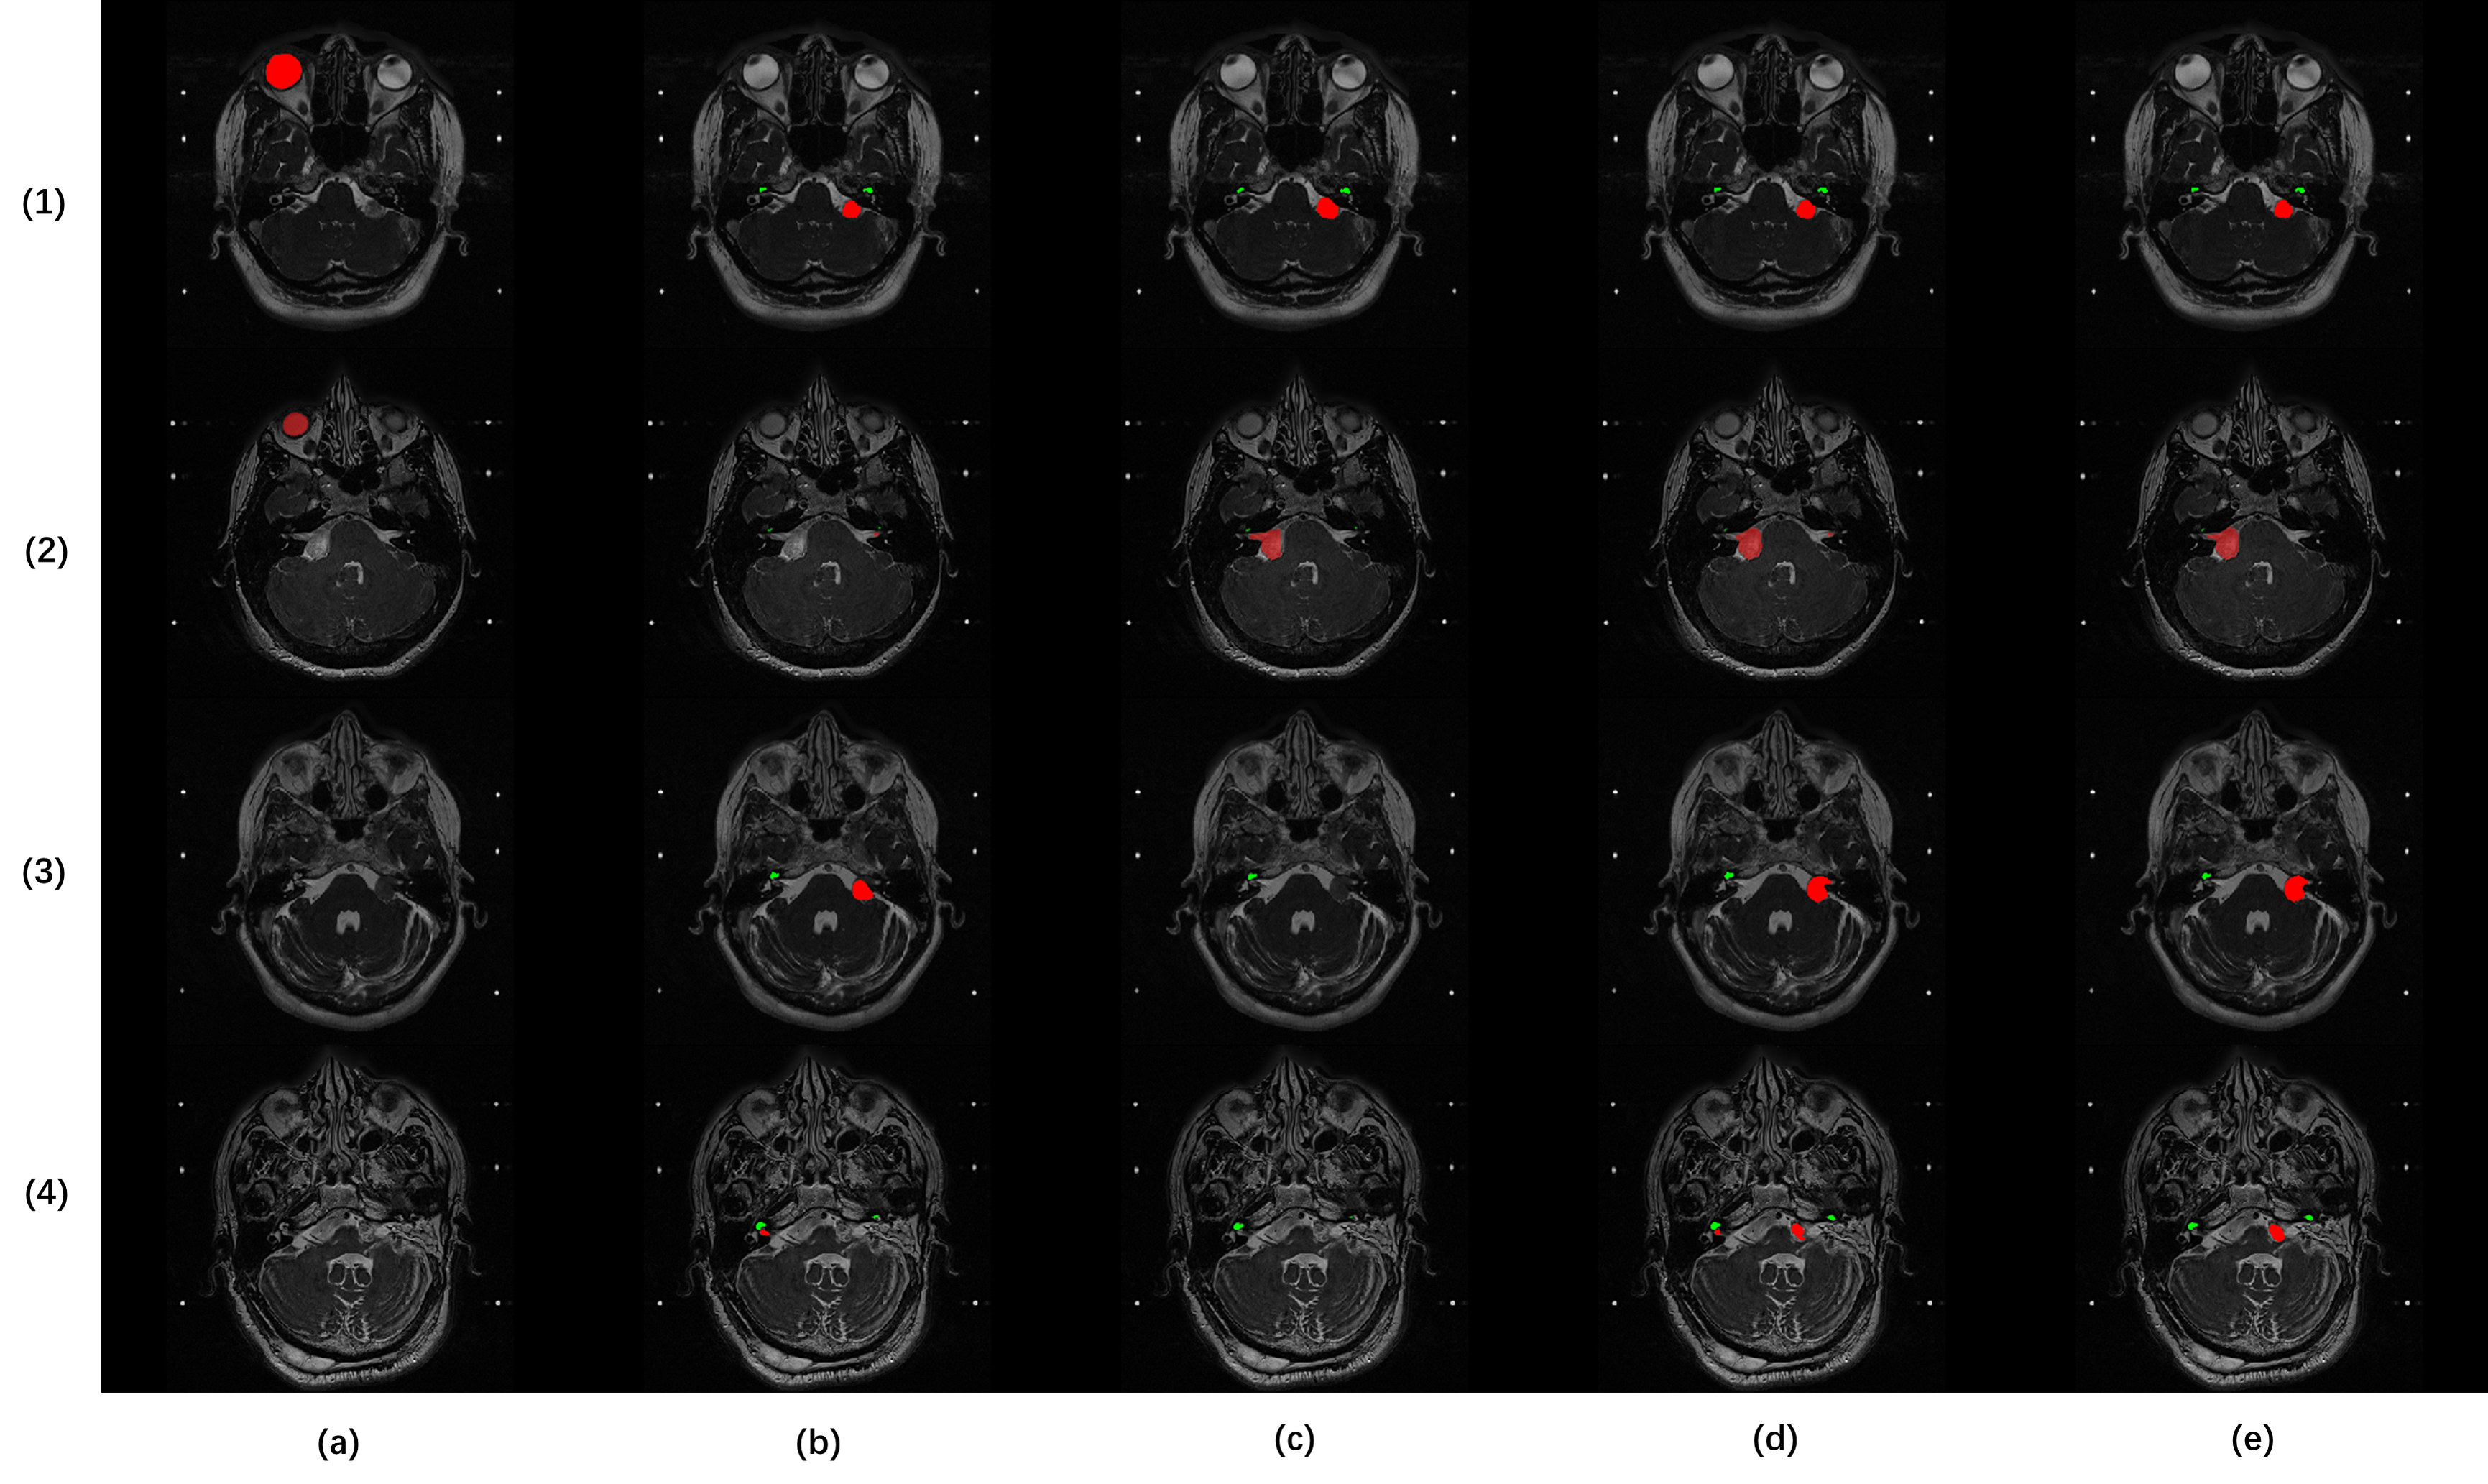

Refer to caption

Figure 3: Visual results of segmentation output : a).nnUnet without DA b).nnUnet448 c).nnUnet384 d).nnUnetST2 e).ResUnetST2 ; Sample id : 1).211(448) 2).213(384) 3).214(448) 4).240(384)

nnUnet384 have a noticeable improvement, which shows the effectiveness of the pixel alignment. However, the two models did not achieve satisfactory accuracy because hrT2 modality itself has two different protocols. nnUnetCon model solves this problem and further improves the performance with model ensembling. Furthermore, the experiments show that self-training achieves better performance on overall Dice, but different network backbones behave differently on either VS or cochlea segmentation (Figure 3). Thus, as our final proposed method, PAST combines all the merits from the aforementioned network architectures and training techniques, raising the overall Dice to 0.8395.